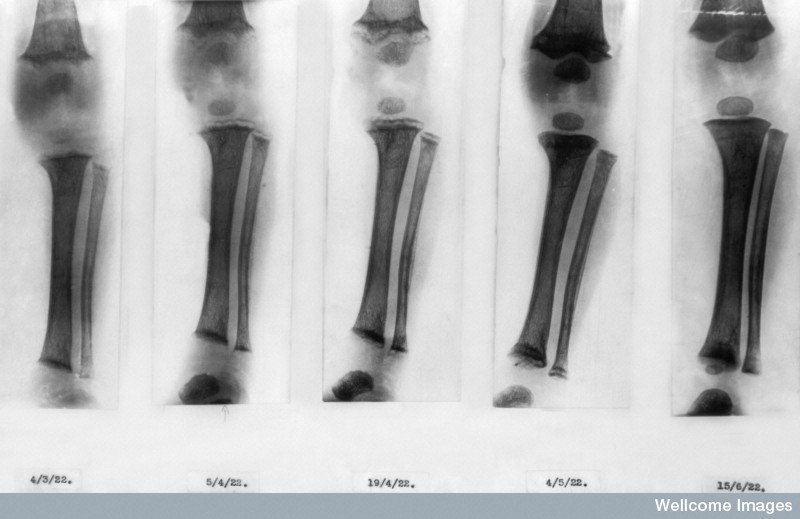

And what a 100 years it has been. You can read about some of our outstanding achievements on our Centenary Timeline including the 1916 discovery that rickets is caused by a lack of Vitamin D, the 1933 finding that flu is caused by a virus, the unravelling of the structure of DNA by MRC researchers in 1953, and the invention of the MRI scanner in 1973. Our scientists also invented DNA fingerprinting in 1984 and helped Parkinson’s disease patients with deep brain stimulation in 1995. More recently we have developed the phone app Txt2stop which doubles a smoker’s likelihood of quitting.